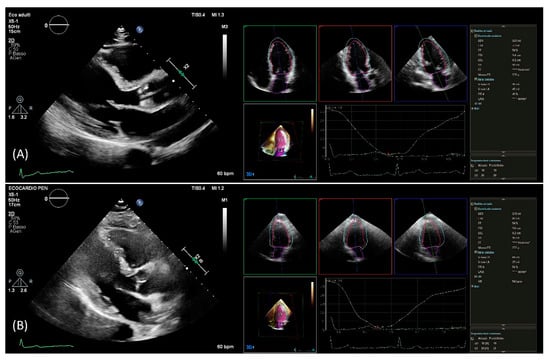

After setting gain, time-gain compensation, and depth on 2D images, a single-beat acquisition mode from the apical 4-chamber view was used to acquire 3D wide-angle datasets. By changing sector width and image depth, the 3D frame rate was optimized. All measurements were performed by the same operator (AB), fully trained in echocardiography with long-standing experience with the 3D technique and trained on echocardiographic datasets with the focus on what constitutes adequate automated analysis. Briefly, the novel vendor software simultaneously detects LV and left atrial endocardial surfaces using an adaptive analytics algorithm, which uses knowledge-based identification to orient and locates cardiac chambers and patient-specific adaptation of endocardial borders from which LV and left atrial volumes are derived directly without geometrical assumptions (Figure 1). LV volumes, left atrial volumes, and ejection fraction were assessed using the 3D method. All measurements were performed online and entered into an electronic database at the time of the echocardiographic study. No modification from the original database was applied, and no measurement was made offline. Hence, the study consisted of a retrospective analysis of data entered into the electronic echocardiographic database.

Figure 1.

PLAX view used for linear 2D measurements and 3D measurements obtained from automated DHM software in a patient with good agreement (A) and in a patient with poor agreement (B) between 2D and 3D mass values. DHM, Dynamic Heart Model; PLAX, parasternal long axis; 2D, two-dimension; 3D, three-dimension.

Using the automated DHM program, which automatically detects LV endo- and epicardial borders at the end-diastole, 3D-LV mass was analyzed, enabling direct LV mass quantification (Figure 1). While it is possible to correct the LV and left atrial endocardial surfaces manually, no changes to the automatically identified cardiac boundaries have been made. Previous studies have shown that LV volumes [8,9,14] and LV mass [12] could be accurately measured using this software, and manual border adjustments led to only clinically insignificant differences. In this study, 3D echocardiography images were analyzed using the same boundary detection sliders for all patients (40 for end-diastole and 10 for end-systole).